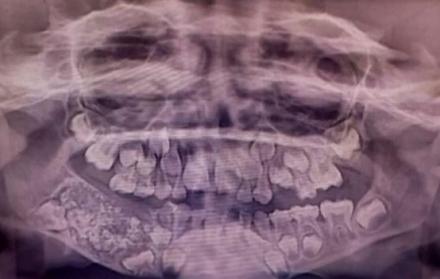

Luego de varios exámenes y diagnósticos, los odontólogos descubrieron una estructura grande y dura, de alrededor 200 gramos. Al retirarla notaron que tenía adentro 526 dientes, cuyas dimensiones iban desde 1 hasta 15 milímetros.

Para los médicos, el niño habría presentado hinchazón en la mandíbula por varios años. Al realizarle una radiografía y tomografía hallaron una estructura con forma de bolsa, conocida como odontoma compuesto.